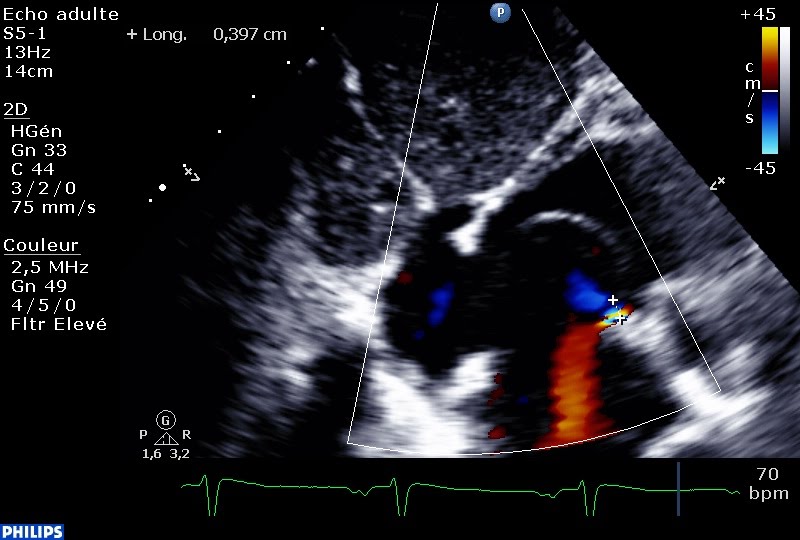

En inspiration profonde, la donne change, la Pression dans l’oreillette droite devient supérieure à celle de l’oreillette gauche, et la grenouille plus grosse que le boeuf. C’est à ce moment précis que le foramen ovale s’ouvre, et la fuite tricuspide s’engouffre dans l’oreillette gauche!

Une fuite tricuspide dans l’oreillette gauche, une fuite mitrale dans l’oreillette droite, c’est à n’y plus rien comprendre!